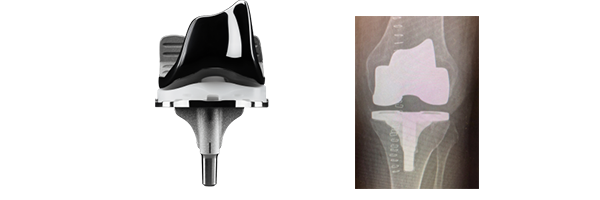

- Les bruits : Le contact entre le plastique et le métal peut engendrer des bruits. Ne vous inquiétez pas. Ce bruit disparaîtra avec le temps.

- La durée de vie de l’implant : taux de survie des grandes séries montrent 85-90% taux de survie à 20 ans de l’intervention.